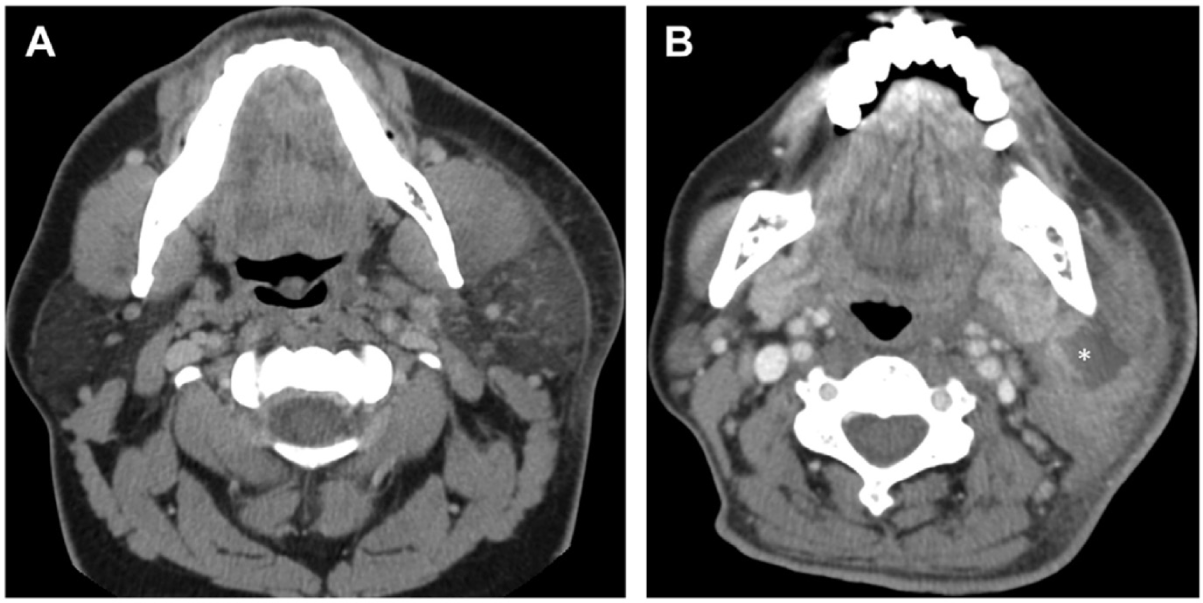

Imaging should be performed in the assessment of suppurative parotitis, especially in cases with suspected complications. Contrast-enhanced CT is particularly valuable for detecting large abscesses or identifying the spread of infection to adjacent structures, which is critical in patients at risk of developing mediastinitis or deep soft tissue infections. Moreover, ultrasound serves as a useful, non-invasive imaging modality to identify abscesses or fluid collections within the parotid gland, aiding in both diagnosis and management planning [37,38] (Figs. 2 and 3).